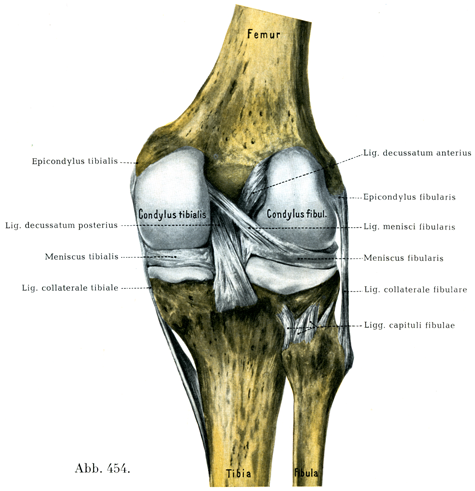

[図454] 右の膝関節(3/4)後方から.関節包は取り去ってある.

b)骨間靱帯は非常に強大で2つあり,たがいに交叉しているので,膝交叉靱帯Ligg. decussata genus, Kreuzbänderとよばれる.この靱帯は滑膜層で被われている.

1. 前交叉靱帯Lig decussatum anteriusは脛骨の前顆間窩Fossa intercondylica anteriorにつき,腓側顆の内側面から起っている.

この靱帯は斜めに前下内側へ走り腓側半月の前端の近くにつき,そのさいこの靱帯の1部の線維束が半月の中に侵入している(図451).

2. 後交叉靱帯Lig. decussatum posteriusは前交叉靱帯より太くて,内側顆の外側面から起り,斜めに後下外側へ走って後顆間窩Fossa intercondylica posteriorに付く.この靱帯の一部でかなり太くて多少とも独立した線維が腓側半月の後部た達している.これは腓側半月靱帯Lig. menisci fibularisとよばれ,その太さは個体によって一定しない(図454).

c)半月Menisciはこの関節における関節面の不一致を均らすのに役だっている.これには腓側半月Meniscus fibularisと脛側半月Meniscus tibialisの2つがある.両半月は弾性線維を混じたかたい結合組織束からなり,その自由表面は線維軟骨でうすく被われている.両者とも鎌形を呈し,横断面では三角柱状である.外面は関節包とかたく結合し,上面は同側の大腿骨願に,下面は脛骨の相当する面に接触している.尖った縁は顆間隆起Eminentia intercondylicaの方に向いている.各半月の両端は強固な線維束で脛骨の一定の場所に固着している(図320, 448).

両半月はこまかい点で相異なっている.内側半月の方がいっそう半月に似た形で,腓側半月の方はむしろ輪に近い.また内側半月は内側側副靱帯と結合しているのに対して,腓側半月は腓側側副靱帯と無関係である.これに反して腓側半月は前方で少数の細い線維束によって前交叉靱帯とつながり,後方ではもっと太い線維束--しばしば非常に太い独立束(腓側半月靱帯Lig. meniscifibularis)によって後交叉靱帯と結合している.両半月は前方で膝横靱帯Lig. transversum genusによってたがいに結合されている.膝横靱帯ははなはだ変異に富む(図448, 451).